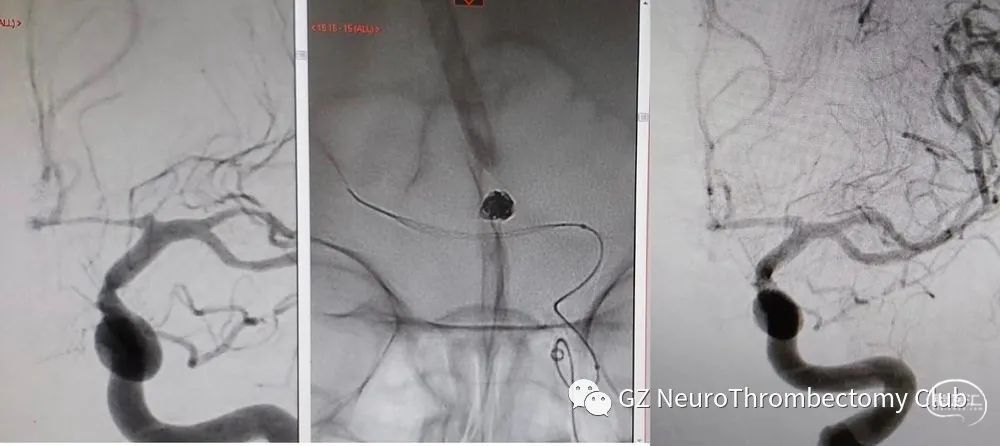

除了主打的辅助栓塞动脉瘤功能之外,Comaneci™ device 又开发出了新用途——治疗SAH导致的血管痉挛,而且还通过了FDA认证。

采用Comaneci™临时推挤机械扩张来改善血管痉挛,在以往动脉注射药物(血管扩张剂)和球囊扩张之间,找到了一种高效且安全的方式。

北美 11 个中心(2020-2022 年),在动脉血管扩张药物无效情况下使用Comaneci™解除血管痉挛。40 例患者(中位年龄52 岁;67.5% 女性)共129 条血管接受机械扩张,其中109 例(84.5%)治疗前存在重度至危重血管痉挛。89.9% 的血管痉挛显著改善(治疗前评分 (3-4) 至治疗后 (0-2))(96.1% 的血管在治疗后评分下降≥1 分)。没有重大术中/术后装置相关并发症。51.5%的患者(中位随访 6个月)有良好临床结果(mRs 0-2)。